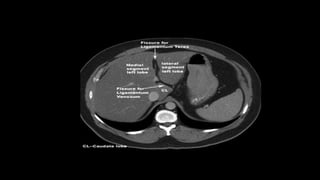

• The left vertical arm of the H -

ligamentum teres anteriorly and the

ligamentum venosum posteriorly.

• The horizontal portion of the H- liver

hilum - porta hepatis.

• The vertical right arm of the H- the

inferior vena cava posteriorly and the

gallbladder fossa anteriorly.

• In the region between the two vertical arms of the H, the two

accessory lobes are recognisable, the caudate lobe posteriorly and the

quadrate lobe anteriorly

LIGAMENTS

• Falciform ligament

• Ligamentum teres

• Ligamentum venosum

• FALCIFORM LIGAMENT:

-Sickle shaped

- Anteriorly connects with peritoneum behind the right rectus

abdominis

- Posteriorly, in contact with left lobe of liver.

- Free edge contain ligamentum teres

- Divides the subphrenic compartment into right and left

• Ligamentum teres or Round

ligament: Formed by obliterated

fetal umbilical vein

• Ligamentum venosum: Formed

by obliterated ductus venosus.

Spans from porta hepatis of the

liver to the inferior venacava.